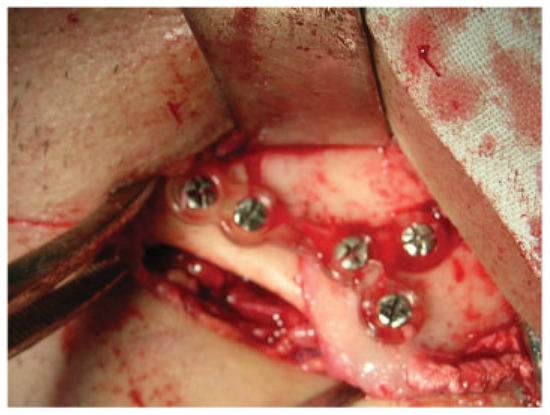

The clinical study was performed at the Department of Oral and Maxillofacial Surgery, Lviv National Medical University, Ukraine, between 2006 to 2010 and included 90 patients with 139 uniand bilateral mandibular fractures of different locations (28 condylar fractures, 88 angle fractures, 15 mental and body fractures, eight symphyseal fractures) treated surgically using HMWPE plates of our own construction and titanium screws (Synthes®, Solothurn, Switzerland; Conmet®, Moscow, Russia Federation) for their fixation. The age of the patients ranged from 18 to 65 years with a mean of 27 years. The indications for osteosynthesis were total or subtotal adentia, considerable displacement of bone fragments, ineffective conservative methods, and patient refusal for prolonged maxillomandibular fixation (MMF). Typical surgical protocol included extraor intraoral exposure of the fracture site (Figure 2) under general or local anesthesia, anatomical reduction of bone fragments (Figure 3), adaptation of the miniplate, drilling of the screw holes depending on preferred monoor bicortical insertion (Figure 4), fixation of the mini-plate with titanium screws (Figure 5), and suturing of the wound. Patients were administered analgesic antibiotics for 5 to 7 days in routine dosages as well as antiseptic solution for regular mouthwash. All patients were observed clinically for 12 to 16 months postoperatively with a mean of 14 months.

A 23-year-old patient was admitted to the Department of Oral and Maxillofacial Surgery at Lviv National Medical University with complaints of swelling of the cheek, intraoral bleeding, and “bad” bite associated with falling from a bicycle. After complete clinical and roentgenological examination, a diagnosis of traumatic fracture in the right mandibular angle area with fragment displacement and impaction of tooth no. 48 in the fracture line was established (Figure 6). He underwent removal of tooth no. 48 from the fracture line, open reduction, and internal fixation of the mandible with two HMWPE miniplates via combined intraoral and transbuccal approaches (Figure 7). A control X-ray obtained the day after osteosynthesis revealed perfect anatomical reduction and fixation of bone fragments (Figure 8). Temporary MMF was maintained for 3 days after osteosynthesis. The postoperative recovery was uneventful, and good mouth opening was achieved. The duration of the patient’s hospitalization was 8 days.

Figure 7. Intraoperative view. An employment of transbuccal system (Synthes®, Solothurn, Switzerland) during fixation of polymeric miniplates.